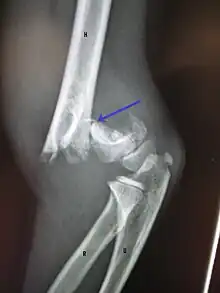

A supracondylar humerus facture is diagnosed by x-ray and the injured limb will be examined to assess the surrounding soft tissue, neurovascular status, and to identify any other injuries to the affected area.[5] Pain, swelling, and deformity near the elbow or arm area is common and a bleed near the fracture may result in an effusion in the elbow joint. With severe displacement, there may be an anterior dimple from the proximal bone end trapped within the biceps muscle. The skin is usually intact. If there is a laceration that communicates with the fracture site, it is an open fracture, which increases infection risk. For fractures with significant displacement, the bone end can be trapped within the biceps muscle with resulting tension producing an indentation to the skin, which is called a "pucker sign".

X-rays

Diagnosis is confirmed by x-ray imaging. Antero-posterior (AP) and lateral view of the elbow joint should be obtained. Any other sites of pain, deformity, or tenderness should warrant an X-ray for that area too. X-ray of the forearm (AP and lateral) should also be obtained for because of the common association of supracondylar fractures with the fractures of the forearm. Ideally, splintage should be used to immobilise the elbow at 20 to 30 degrees flexion in order to prevent further injury of the blood vessels and nerves while doing X-rays. Splinting of fracture site with full flexion or extension of the elbow is not recommended as it can stretch the blood vessels and nerves over the bone fragments or can cause impingement of these structures into the fracture site.[3]